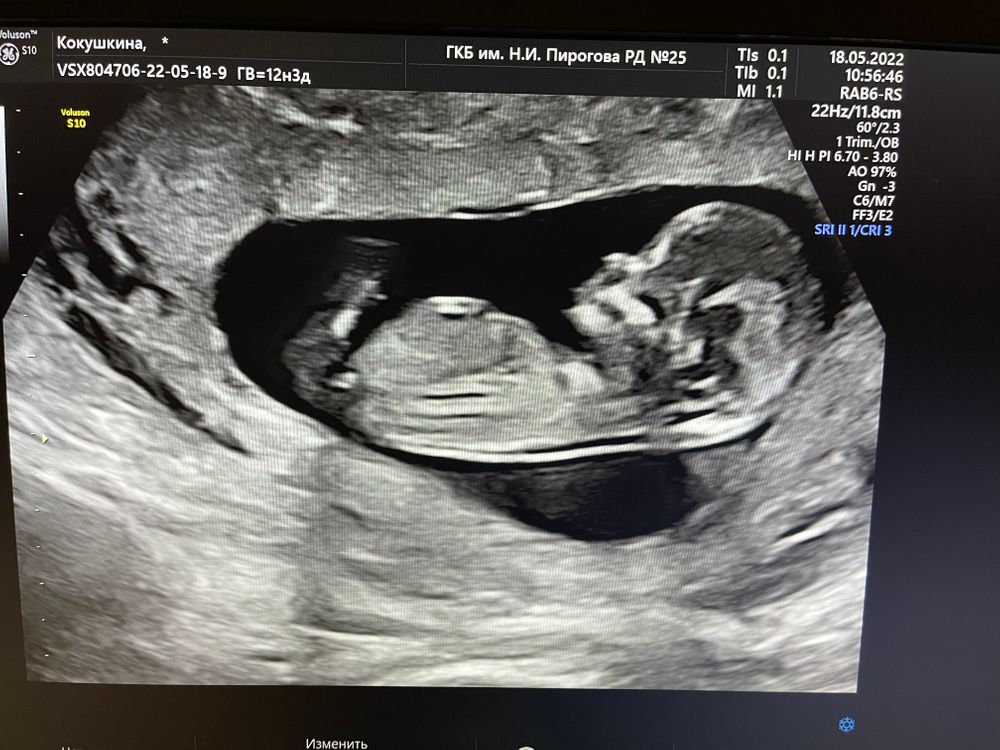

Первый пост со скрининга я уже выкладывала чуть более недели назад. Но не просила предположить пол, так как бугорка не видно. Но мне все же интересно мнение, пусть и пальцем в небо)))

На скрининге врач сказала так «похож на мальчика»

Я помимо бугорка опираюсь ещё на форму животика малыша. Не помню точно где, но слышала, что у мальчиков животик больше, чем у девочек. Для примера сравнение с предыдущими детьми девочками (с мальчиками не было фото с первого скрининга)